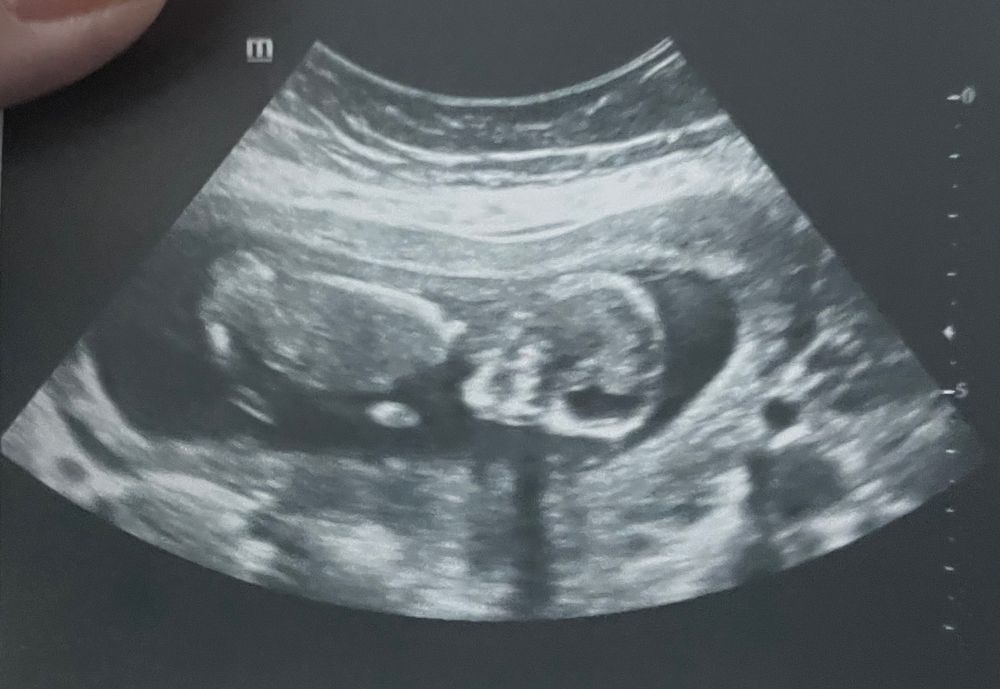

Алена, вот наш вроде 7 недель чет понятно? 😂 Изображение

Яна, понятно, что ничего не понятно🤣🤣🤣

Белк@, да😂муж так же сказал че там можно увидеть 😂

Яна, плохо видно, не вижу эмбриона